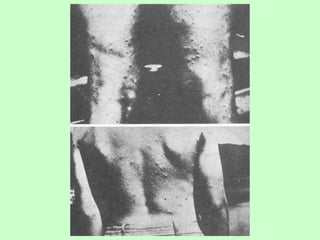

Sintomas

• Problemas no fígado,

baço e intestino;

• Diarréias, dores

abdominais e

emagrecimento;

• Hepatoesplenomegalia;

• Ascite;

• Dermatites cercarianas

e coceiras.

Sintomas • Problemas nofígado, baço e intestino; • Diarréias, dores abdominais e emagrecimento; • Hepatoesplenomegalia; • Ascite; • Dermatites cercarianas e coceiras.